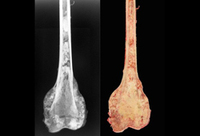

Osteossarcoma osteoblástico do fêmur distal (radiografia e fotografia do espécime macroscópico)

Do acervo do Dr. Michael J. Klein e da Dra. Luminita Rezeanu